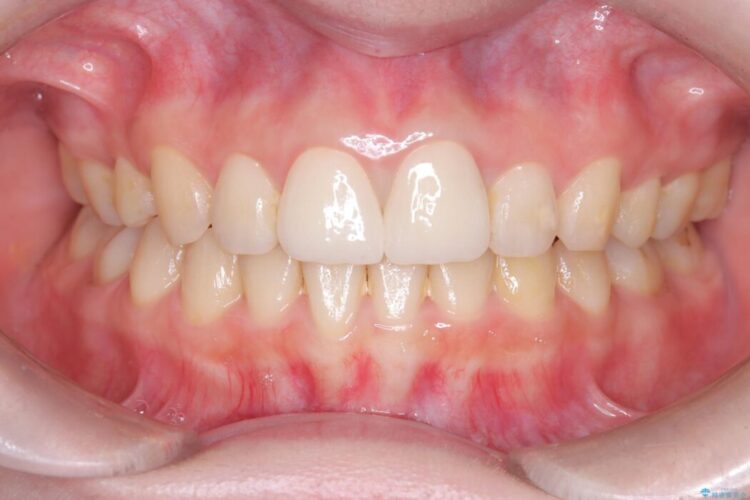

メタルフリー|全ての銀歯をセラミックへ

メタルフリー|全ての銀歯をセラミックへ ビフォー メタルフリー|全ての銀歯をセラミックへ アフター

口腔内の銀歯を全て無くし、白く健康的な状態にしたいとご来院された患者様です。